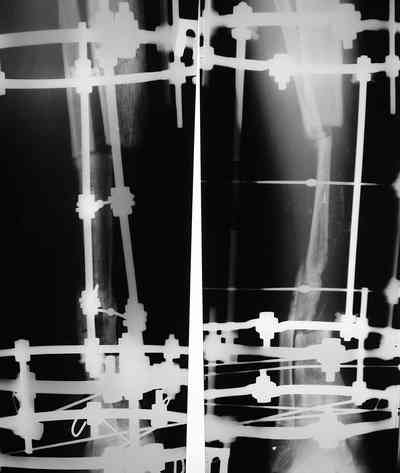

Владимир, свободная костная пластика на фоне свища вряд ли оправдана. Почему не рассматриваете вариант транспорта кости по Илизарову? Что собираетесь делать с латентной инфекцией? Одни антибиотики не помогут, необходима полноценная хирургическая обработка, Мы бы подумали о цементном спейсере с антибиотиками, бусах. После купирования инфекции переходить к замещению

дефекта: за счет удлинения концов б\б кости или тибиализации м\б. На начальном этапе фиксация только в аппарате, в последствие для удержания достигнутого можно перейти на фиксацию интрамедуллярным штифтом (см. вложенные файлы)